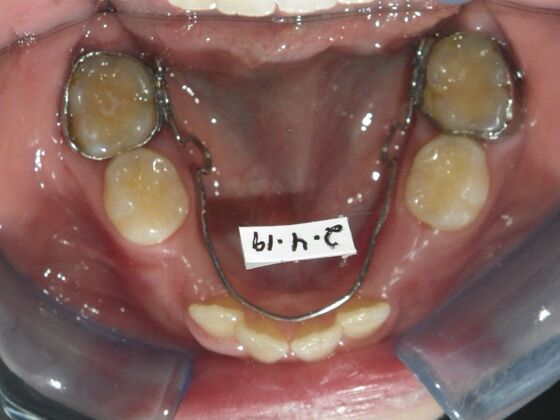

Orthodontics: Case 43

Patient presented with mixed dentition and mild deep overbite, excessive overjet,and rotated lower incisors. She also had a lower bilateral lingual retainer, preventing lower molars from coming forward. She was treated with utility archwires initially, waiting for eruption of cuspids and bicuspids. This was followed by conventional straight wire appliances and upper and lower standard hawley retainers.